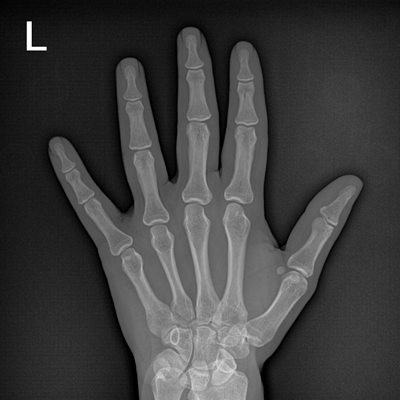

輕量化設(shè)計(jì) 小巧靈活 PLX5100

用于影像科、急診室、病房、ICU、手術(shù)室等多場(chǎng)景應(yīng)用。

● 數(shù)字化無線平板成像,操作簡(jiǎn)便,成像質(zhì)量高

● 配備移動(dòng)筆記本,無線圖像采集,無線PACS傳輸